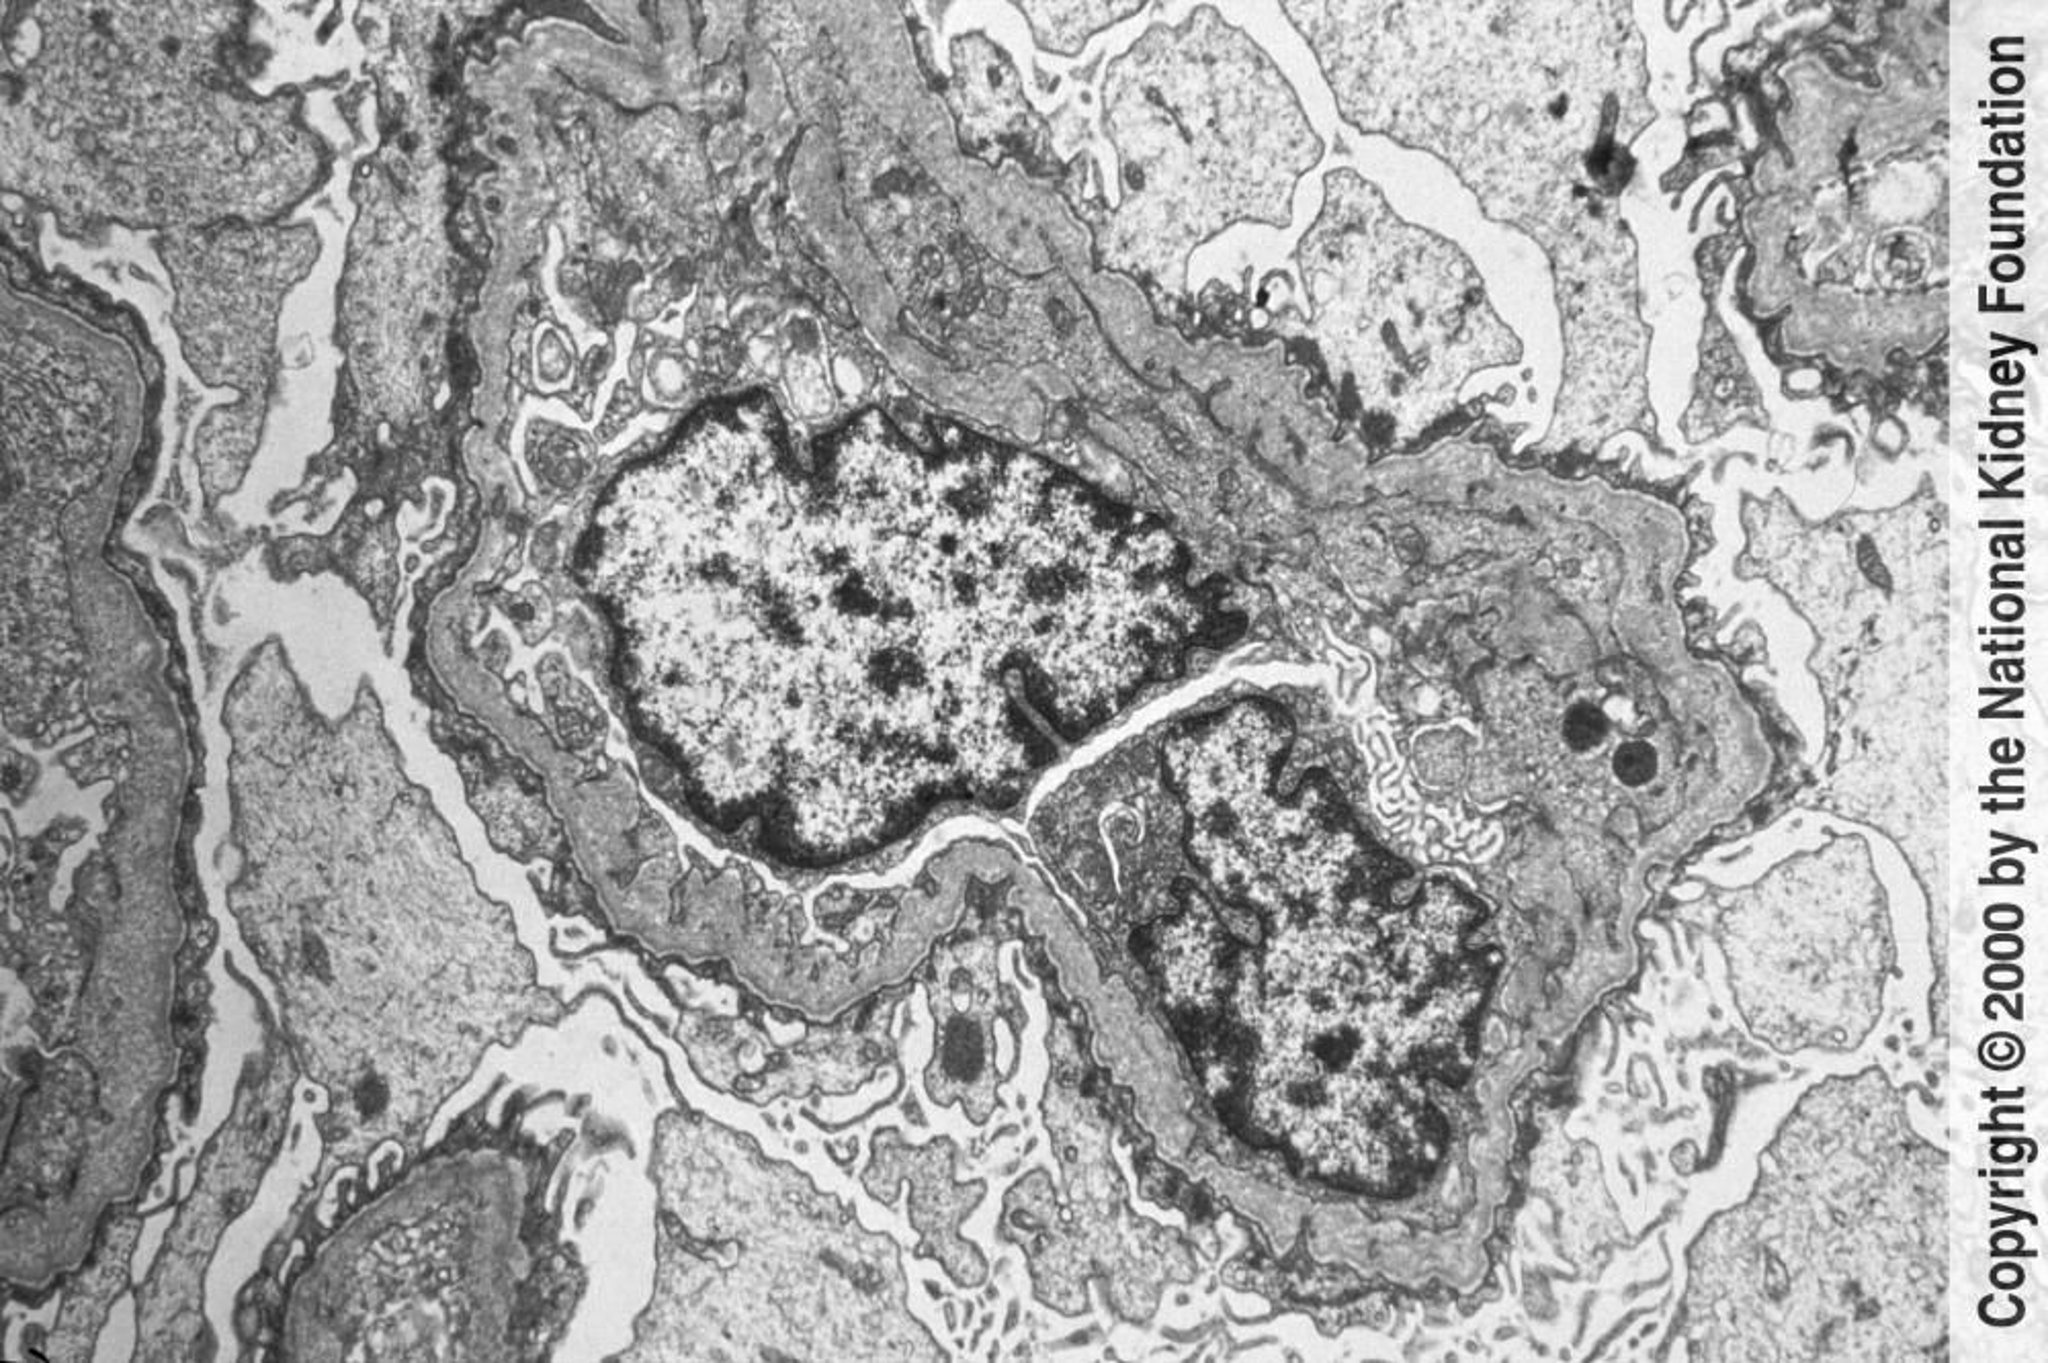

Syndrome d'Alport (néphrite héréditaire)

Les membranes basales glomérulaires montrent un amincissement et un épaississement irréguliers avec un aspect lamellé en forme de nacelle en microscopie électronique à transmission. Les modifications sont causées par les blessures et le remodelage (×6000).

Image fournie par Agnes Fogo, MD, and the American Journal of Kidney Diseases' Atlas of Renal Pathology (voir bwww.ajkd.org).